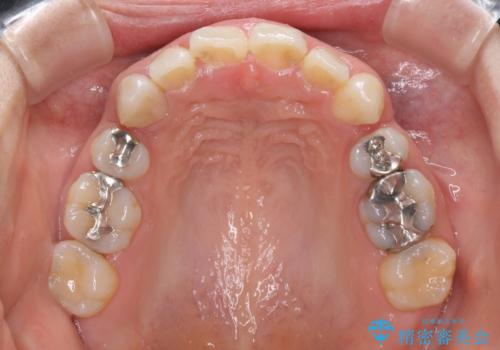

インビザラインにて抜歯矯正を行うと、高頻度で奥歯が咬み合わなくなります。

抜歯スペースが閉じてからも咬みにくさ改善のためマウスピース矯正を継続するため、治療期間は長期化します。